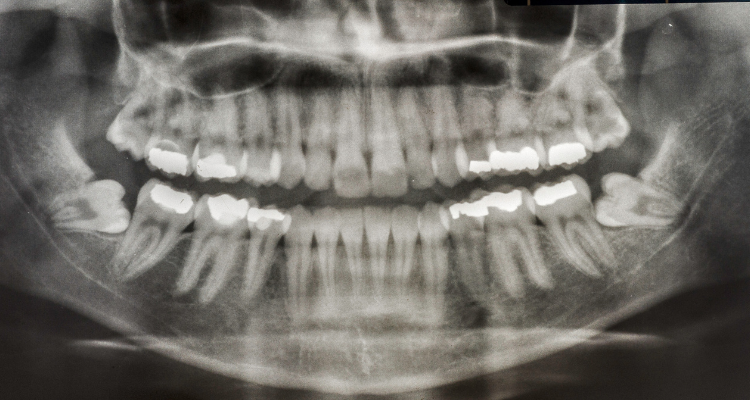

The most common type of impacted tooth are wisdom teeth, also known as third molars. These teeth usually erupt in a person’s late teens or early 20s, when a person is older and presumably wiser. However, these teeth have been known to erupt at any time during adulthood. Because these teeth are the last to erupt, there is usually not enough space for them to come in properly, and they need to be removed to preserve a person’s oral health.

The second most common problem is with impacted canines. These teeth are located on each side of the incisors and give your smile a symmetrical appearance, as well as helping you grip and tear your food. In most cases, removing the gum tissue around the tooth can solve the problem, although there may be instances when additional orthodontic work will be required to move the tooth into the proper position.